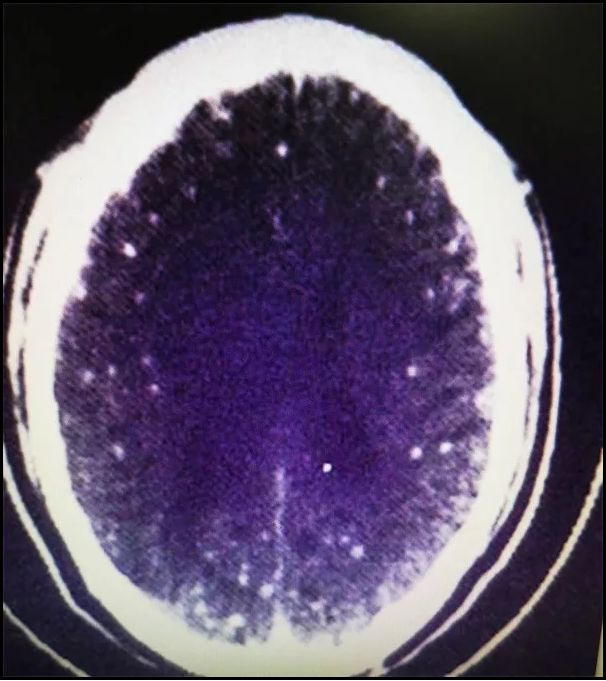

△颅内CT显示有多个白点病变(来源:浙大一院)

就医检查后,医生发现,朱先生患了脑囊虫病。

对此,医生解释,之所以寄生虫会出现在朱先生的脑子里,问题不是出在火锅本身,而是涮的猪肉、羊肉可能本身有猪囊尾蚴虫寄生,吃火锅时,肉没有涮熟透,导致猪囊尾蚴虫通过消化道进入了脑子。